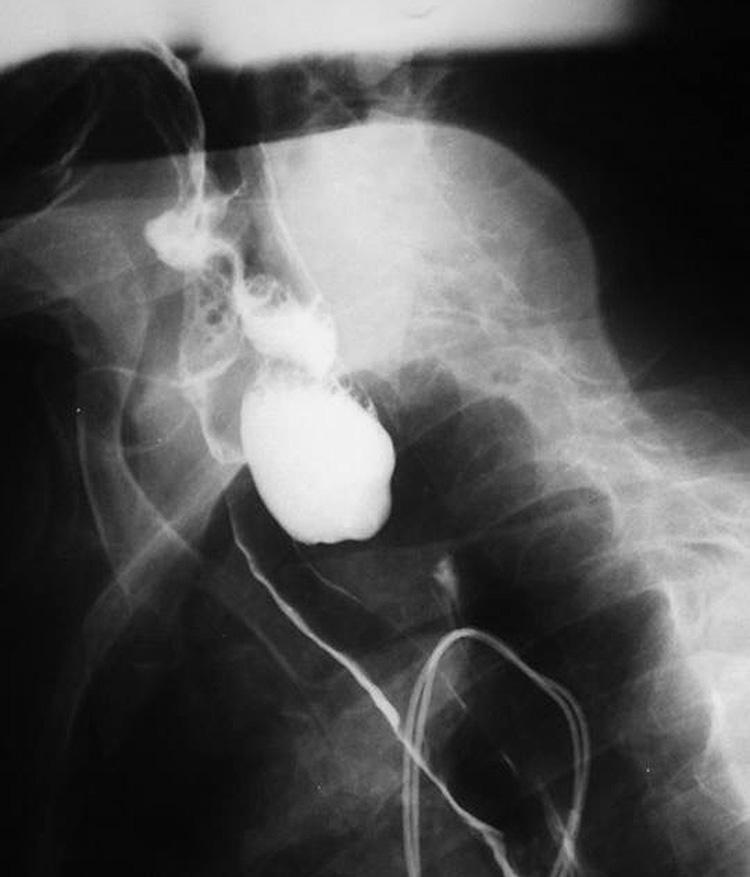

Divertículo de Zenker

Zenker's diverticulum

Caso Código 133A de Divertículo de Zenker - Case Code 133A of Zenker's diverticulum

Rx contrastado do esôfago revelando divertículo de Zenker.